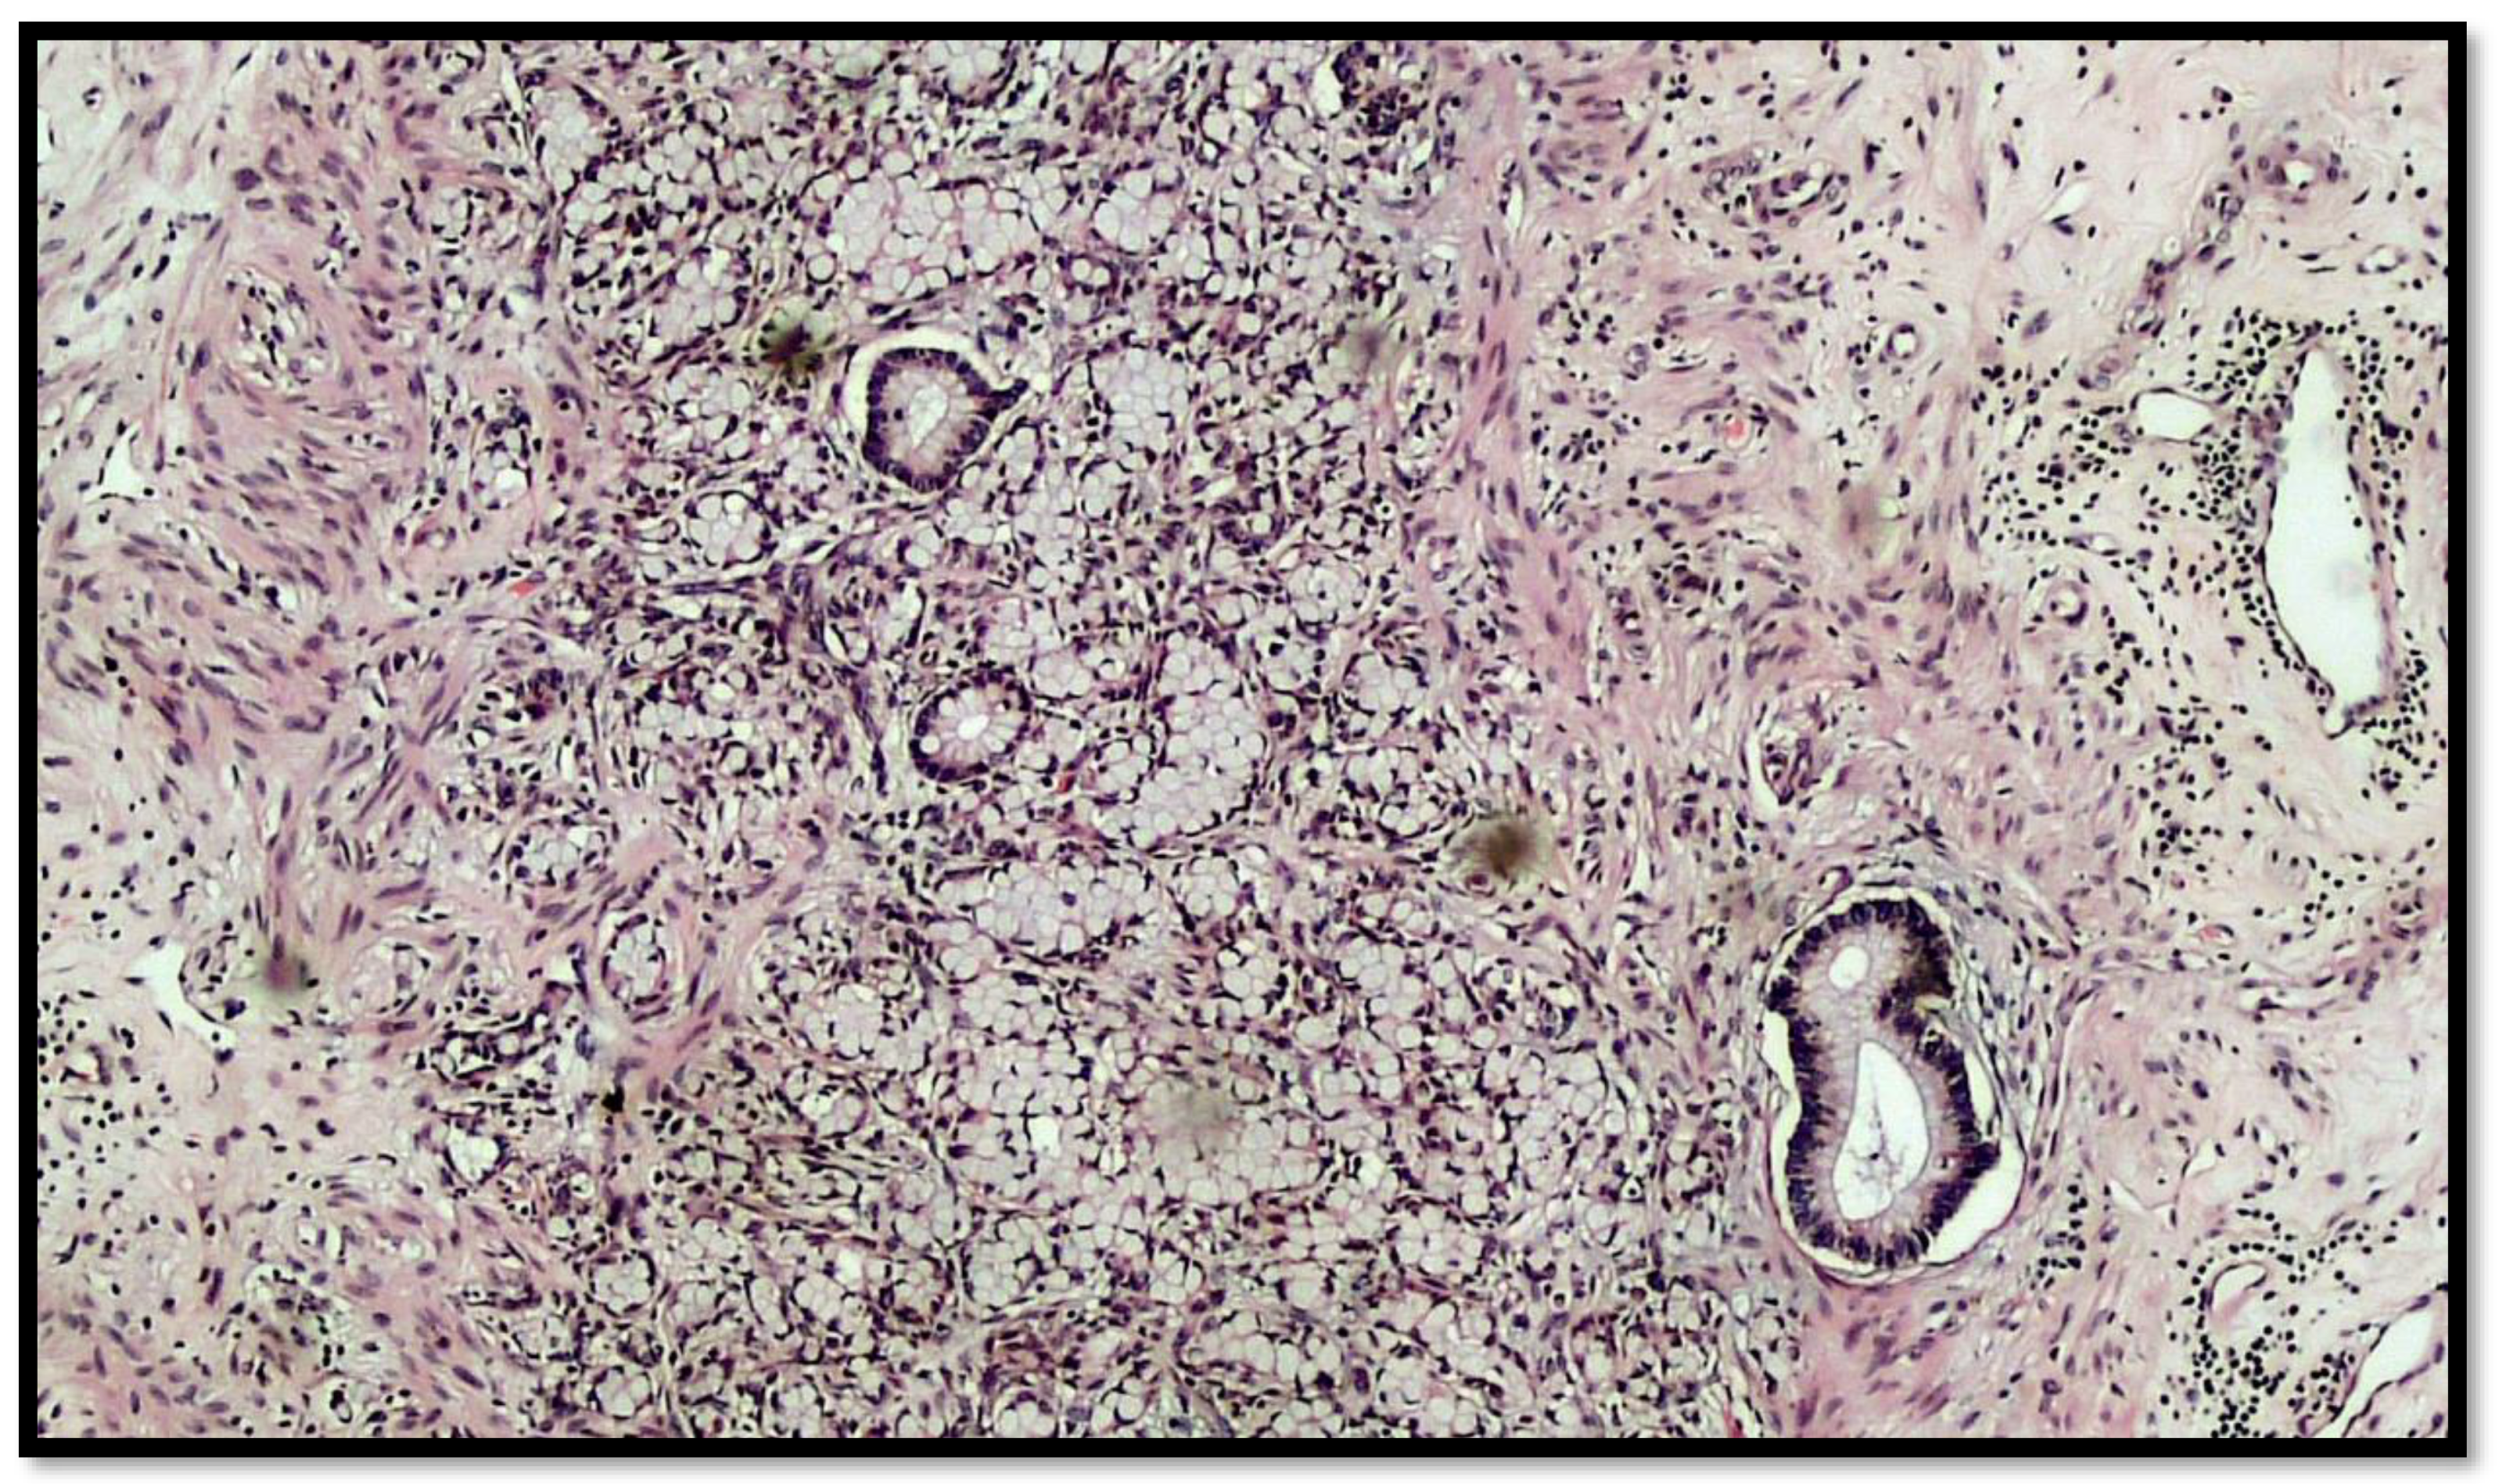

Figure 2.

Photomicrograph showing goblet cell carcinoid of the appendix. Cytological detail of the “ring with bezel” cells (hematoxylin–eosin, original magnification: 20×). An example of a ring with bezel cells is indicated with a red arrow.

Figure 3.

Another photomicrograph showing goblet cell carcinoid and some glands in the muscular wall of the appendix. (Hematoxylin–eosin, original magnification 20×).